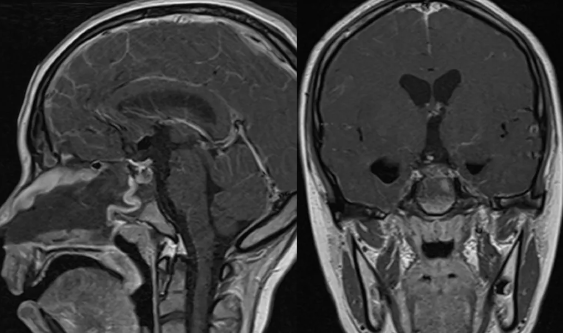

经过多方打听得知附属新华医院神经外科在颅咽管瘤治疗方面很有经验,王旭辉主任是经鼻内镜治疗颅咽管瘤和垂体瘤的专家。于是专程前往附属新华医院就诊,王主任首先给小潘开具了磁共振检查(图1),检查发现小潘得的是一种在儿童及青少年并不罕见的疾病,颅咽管瘤。

图1:术前磁共振检查

小潘的颅咽管瘤十分巨大,从垂体窝一直向上生长突破鞍隔并长穿第三脑室底。王旭辉主任向老潘一家详细的介绍了病人的病情,虽然肿瘤很大,位置也很深,肿瘤周围都是十分重要的结构,而且青少年的鼻腔还相对较小,但依然可以通过经鼻内镜微创的方式将小潘的颅咽管瘤全部切除。小潘一家听到后十分激动,这就是他们追寻的小创伤方案,于是小潘入院后,快速的完善了术前检验检查,入院后第三天小潘在全麻下开始手术。